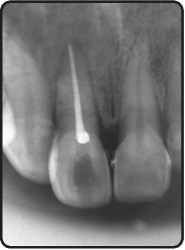

Endodontic Therapy: We specialize in the diagnosis and treatment of infected, inflamed or necrotic pulp, utilizing advanced techniques following the principles of minimal invasive dentistry.

Endodontic Treatment Outcomes: We meticulously evaluate the long-term success and efficacy of various endodontic treatment modalities by using and comparing various Endodontic files, Irrigating Solutions and Sealers along with Obturating materials.